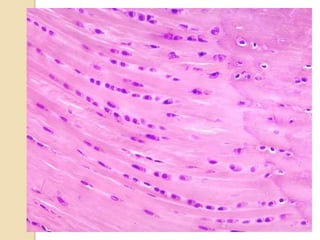

 Fibro cartilage consists of

chondrocytes dispersed

among bundles of type 1

collagen fibers.

 Chondrocytes are

present in lacunae

(cavity).

 The arrangement of

cells is different from all

other type of cartilages.

arranged in parallel rows

of 2, 4 or 6 cells.

 These rows of cells

are called isogenous

cell groups.

 Due to the abundance of collagen type

1 fibers , the matrix of fibrocartilage

stains intensely

acidophilic/eosinophilic. (since

collagen is basic in nature)

 Stained by EOSIN which is pink in

color.

 Chondrocytes are stained in purple

usually by HEMATOXYLIN and looks

purple in color due to acidic nature of

Occurrence in body